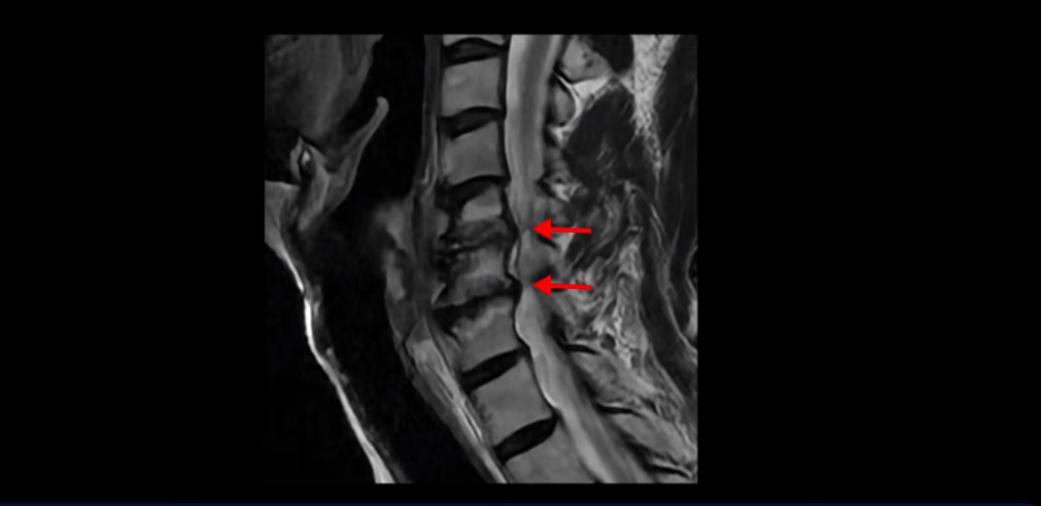

먼저 이분 MRI와 X-ray 보면서 간단히 설명해 드린 후 어떻게 목 협착증으로 신경이 눌려서 극심한 목통증과 견갑골 통증이 몇 달씩 지속되고, 고개가 조금도 돌아가지 않고 하루 24시간 아파서 잠도 잘 수 없는 환자가 수술 없이 비수술 치료로 좋아질 수 있는지, 치료는 어떻게 하는지 자세히 설명해 드리겠습니다. 참고로 이 환자분의 치료 후기는 2개입니다. 이분은 허리에도 심한 전방전위와 협착이 있어서 목 치료와 함께 허리 치료도 받으셨고, 허리 치료 후기 영상도 있으니 별도로 보시길 바랍니다.

이분 목 X-ray를 보면 역C자형의 목에 전방전위도 보이고,

두 마디의 디스크가 거의 닳아서 뼈들이 거의 붙어 보입니다.

목도 많이 휘어 보입니다.

MRI를 보면 2마디 디스크의 퇴행이 아주 심해 보입니다.

그래서 오른쪽 신경 가지가 빠져 나가는 추간공 2개와

왼쪽 추간공 두 개가 모두 많이 좁아져 있습니다.

이렇게 신경 구멍들이 좁아져 있고 신경 주사가 효과가 없으니까 동네 정형외과에서는 무조건 대학병원으로 가라고 했는데요. 가서 수술 받으라는 얘기겠죠. 그런데 저희 모커리한방병원은 협착증은 수술 없이 치료가 잘 될 수 있는 질환이라고 계속 설명하고 있는데요. 왜 그럴까요? 저희가 협착증이 왜 수술 없이 치료 가능하다고 설명하는지에 대해 잘 이해하시려면 무증상 협착이라는 개념에 대해 잘 이해하셔야 합니다.